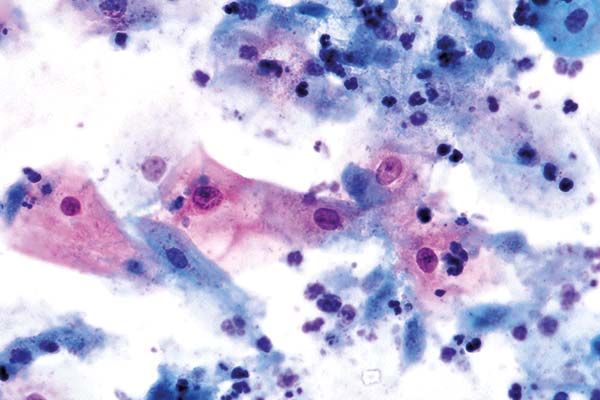

Oktober

richtige Antwort:

d. Trichomonadenkolpitis (I)

- Vorkommen meist mit bakterieller Mischflora

- Unscheinbare Gebilde mit zyanophilem Zytoplasma

- Angedeuteter Zellkern und rote Körnelung im Zytoplasma

- Starke entzündlich degenerative Begleitreaktion